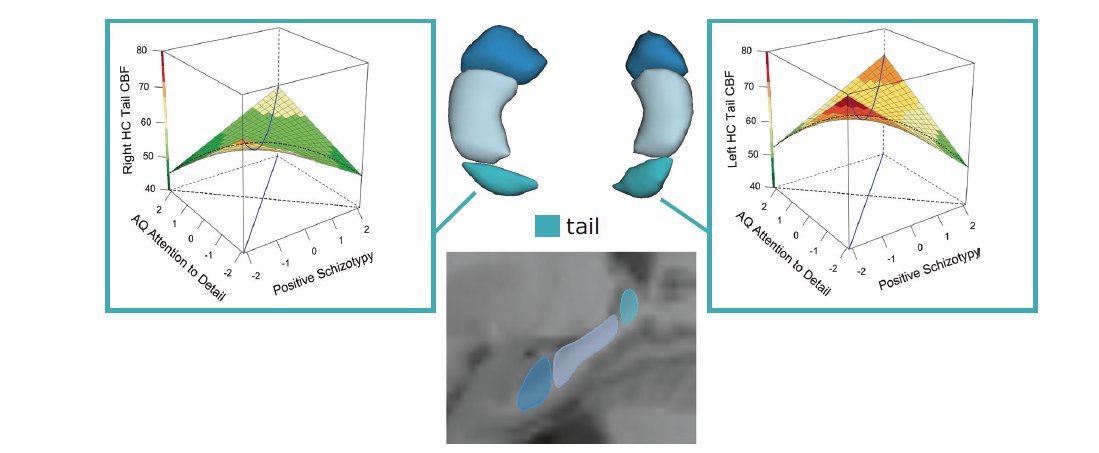

Exciting new paper collaborating with Igor Nenadic, Ahmad Abu-Akel, Dr. Tina Meller et al. Hippocampal subfield volume and CBF are linked to an interaction of schizotypy traits with autism traits in a large sample of healthy subjects. doi.org/10.1038/s41380… molecularpsychiatry